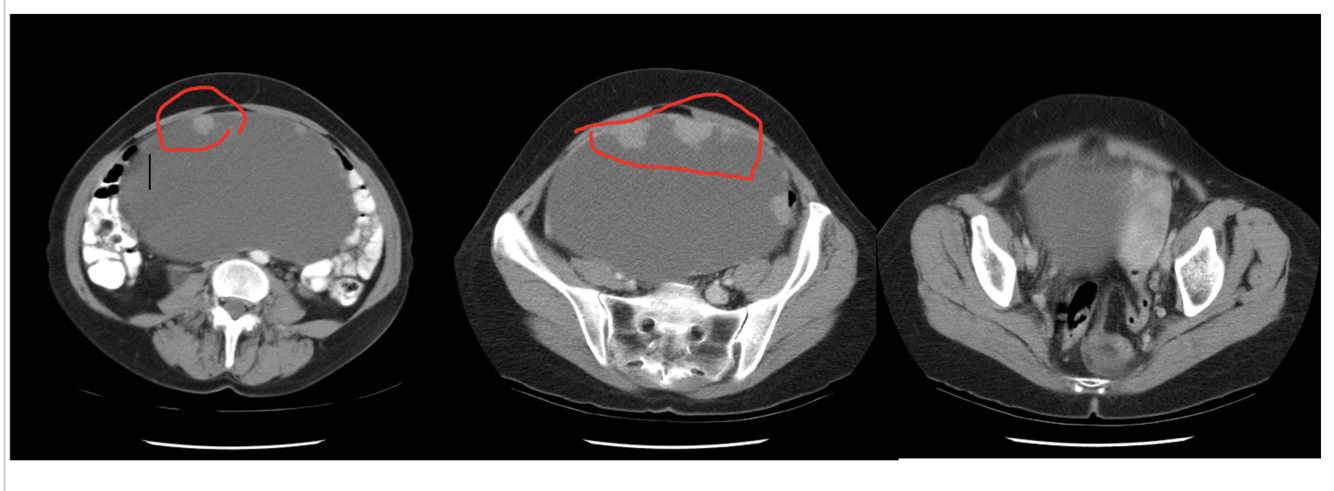

What this be?

Cystadenocarcinoma (tissue density changes circled in red help in identification)